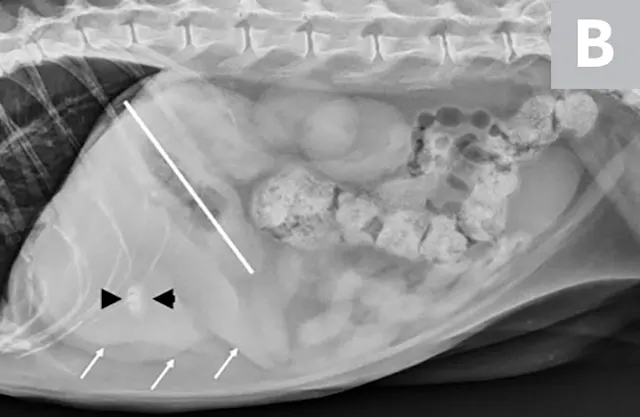

FIGURE 1A

Lateral radiographs of a clinically normal cat (A) and a 14-year-old neutered male domestic shorthair cat (B) presented with icterus and elevated liver enzymes. A normal feline liver should have a sharp, pointed margin (A; arrows) and should not extend past the costal arch; the gastric axis should be parallel to the ribs (A; line). The liver in the icteric cat extends past the costal arch, and has rounded borders (B; arrows). The stomach is displaced caudally (B; line; gastric axis from the fundus to the antrum). An ovoid mineralization (B; arrowheads) is also superimposed with the cranioventral liver in the location of the gallbladder. This cat was diagnosed with cholangitis, lipidosis, and a cholelith.